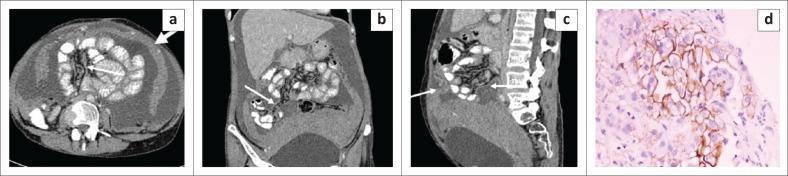

Ultrasound and computed tomography in the evaluation of mesenteric lesions: A pictorial review.

The mesentery is a broad fan-shaped fold of peritoneum that suspends the loops of small intestine from the posterior abdominal wall. Although primary neoplasms arising in the mesentery are rare, the mesentery is a major avenue for the dissemination of tumours, which can spread through hematogenous, lymphatic, direct or peritoneal seeding. Imaging helps in the diagnosis of these tumours and aids in directing appropriate treatment by assessing their size, extent and relationship with adjacent structures. The aim of this article is to describe the spectrum of imaging findings of the various mesenteric lesions using ultrasound and CT.

Evaluation of the mesentery is often neglected during routine ultrasound (US) because of inadequate training and unfamiliarity with the common US features encountered with mesenteric disease. CT plays an essential role in the diagnosis of mesenteric disease. Knowledge of imaging characteristics of various mesenteric lesions helps in timely diagnosis and management.